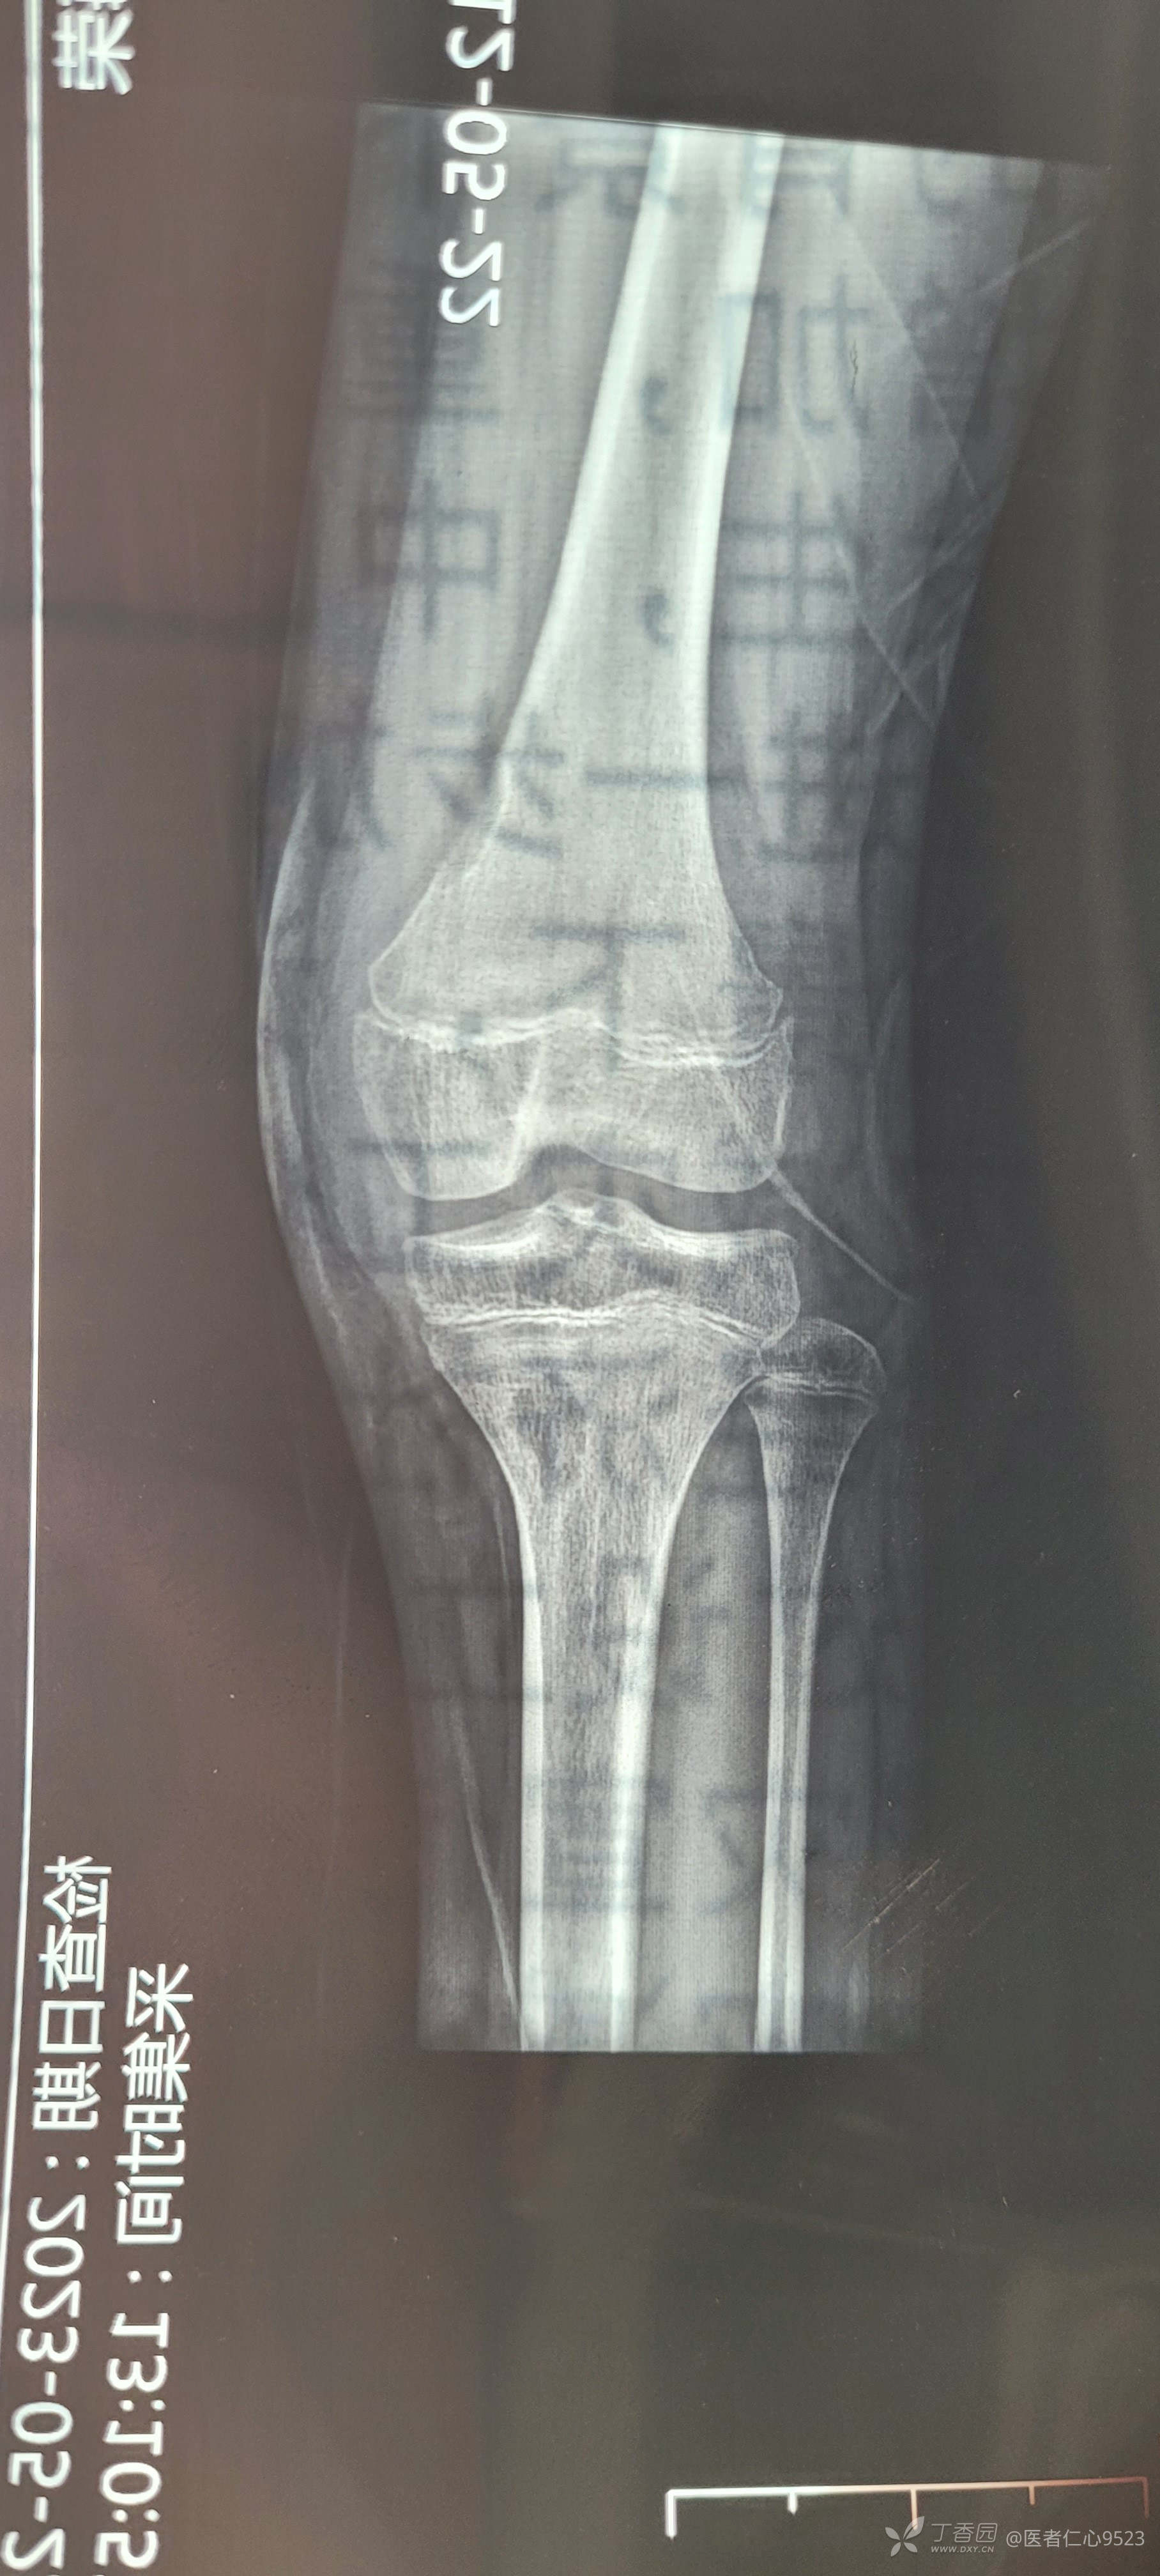

患者为13岁学生,二周前踝关节扭伤,给与石膏固定,三天前无明显诱因出现同侧膝关节疼痛伴肿胀,行膝关节X线发现胫骨平台下方低密度影,患者白细胞1.4万,中性粒细胞比例70,皮肤无破损,近期无感冒史,迷惑的地方是白细胞虽然不是特异性高,但是患侧膝关节肿胀疼痛明显,求哪位给点思路